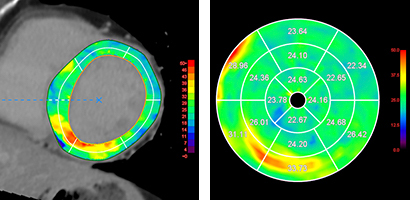

Ziostation2のCT心筋ECV解析ではCTで撮影した遅延造影相のデータと単純相のデータを読み込み後,自動位置合わせと差分の計算(サブトラクション)し,左室内腔のCT値とヘマトクリット値を利用して細胞外液分画(ECV:Extra Cellular Volume)を算出します。また心筋の自動抽出機能を有しており,心筋上へのECVのオーバーレイ表示やBull’s eye mapを表示し心筋評価を行えます。

CT心筋ECV解析(左:心筋輪郭自動抽出,右:Bull’s eye map)